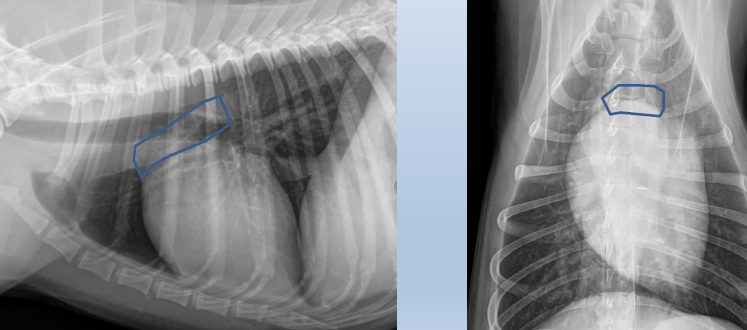

Lateral

2 to 5 left ventricle

5 to 9

Right ventricle

9 to 11

Pulmonary artery

Aortic arch

Right auricle

12 to 2

Left atrium